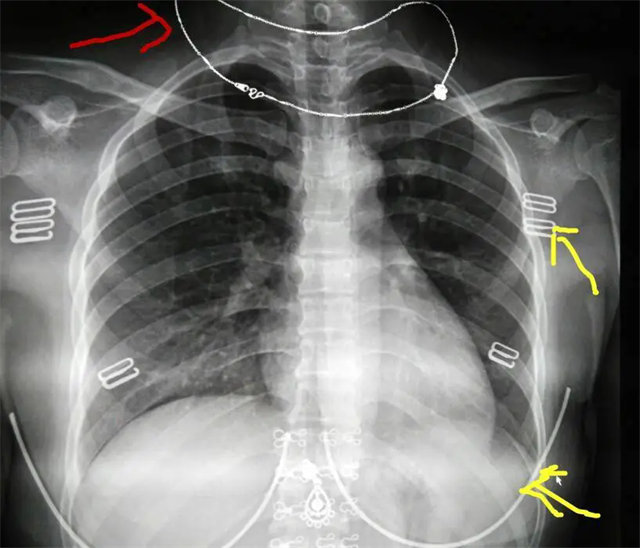

缺陷:肩胛骨未完全拉離肺野,吸氣不完全,存在金屬偽影遮擋,略有聳肩,且肺尖顯示不好,圖像顆粒感較強,管電流量不夠,信噪比偏低。

解決:去除金屬物品后,按標準體位,使患者雙肩旋前與前胸一并緊貼成像件,適當調高mAs,然后深吸氣后屏氣曝光。